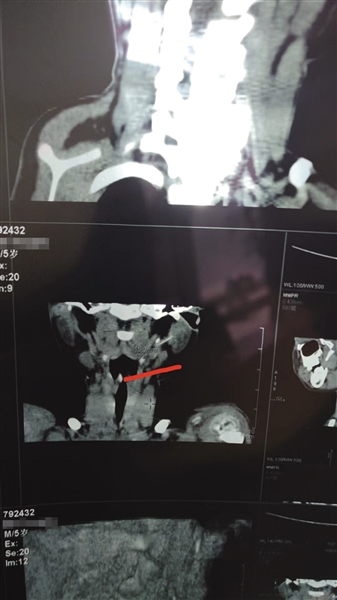

4月7日,星元医院CT结果显示,软管目前位于小白颈部左侧腮腺内。 本版图片/受访者供图

不做手术任由软管继续留在体内也有风险。2024年4月7日,星元医院CT结果显示,软管目前位于小白颈部左侧腮腺内。白海海告诉新京报记者,小白今年已经在上幼儿园大班,软管留置体内的5年多,“娃娃没说过身体不舒服,也没有特别的感觉”,但西安市儿童医院出院记录上的一行字像根刺一样扎在他心上——“考虑(异物)已在血管内漂移,可能至心、肺部”,他担心,这截随着血液游动的软管早晚有一天会像炸弹一样引爆,影响小白的健康,甚至危及生命。